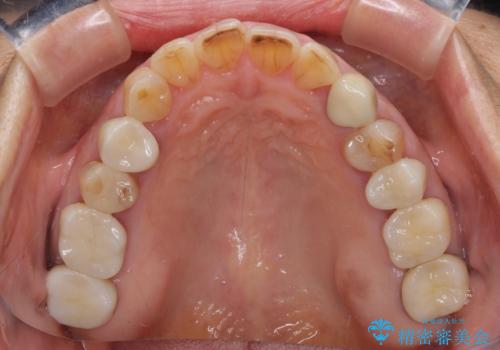

全ての奥歯の銀歯をセラミックに メタルフリー治療

途中体調を崩されてしまい、その間に仮歯が外れてしまうなど、治療期間が長引いてしまいました。

治療期間はかかってしまいましたが、念願のメタルフリーとなり、患者様には大変満足していただきました。